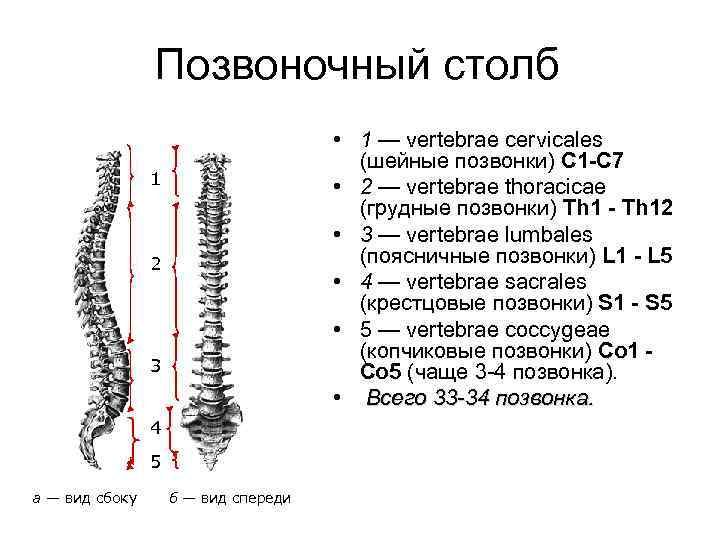

Позвоночный столб • 1 — vertebrae cervicales (шейные позвонки) C 1 -С 7 • 2 — vertebrae thoracicae (грудные позвонки) Th 1 - Th 12 • 3 — vertebrae lumbales (поясничные позвонки) L 1 - L 5 • 4 — vertebrae sacrales (крестцовые позвонки) S 1 - S 5 • 5 — vertebrae coccygeae (копчиковые позвонки) Со 1 Со 5 (чаще 3 4 позвонка). • Всего 33 -34 позвонка. 1 2 3 4 5 а — вид сбоку б — вид спереди

Позвоночный столб (columna vertebralis) настоящая основа скелета, опора всего организма. Конструкция позвоночного столба позволяет ему, сохраняя гибкость и подвижность, выдерживать ту же нагрузку, которую может выдержать в 18 раз более толстый бетонный столб. Позвоночный столб отвечает за сохранение осанки, служит опорой для тканей и органов, а также принимает участие в формировании стенок грудной полости, таза и брюшной полости. Каждый из позвонков (vertebra), составляющих позвоночный столб, имеет внутри сквозное позвоночное отверстие (foramen vertebrale). В позвоночном столбе позвоночные отверстия составляют позвоночный канал (canalis vertebralis), содержащий спинной мозг, который таким образом надежно защищен от внешних воздействий. Во фронтальной проекции позвоночника явственно выделяются два участка, отличающиеся более широкими позвонками. В целом масса и размеры позвонков увеличиваются по направлению от верхних к нижним: это необходимо, чтобы компенсировать возрастающую нагрузку, которую несут нижние позвонки. Помимо утолщения позвонков, необходимую степень прочности и упругости позвоночнику обеспечивают несколько его изгибов, лежащих в сагиттальной плоскости. Четыре разнонаправленных изгиба, чередующиеся в позвоночнике, расположены парами: изгибу, обращенному вперед (лордозу), соответствует изгиб, обращенный назад (кифоз). Таким образом, шейному (lordosis cervicalis) и поясничному (lordosis lumbalis) лордозам отвечают грудной (kyphosis thoracalis) и крестцовый (kyphosis sacralis) кифозы. Благодаря такой конструкции позвоночник работает подобно пружине, распределяя нагрузку равномерно по всей своей длине.